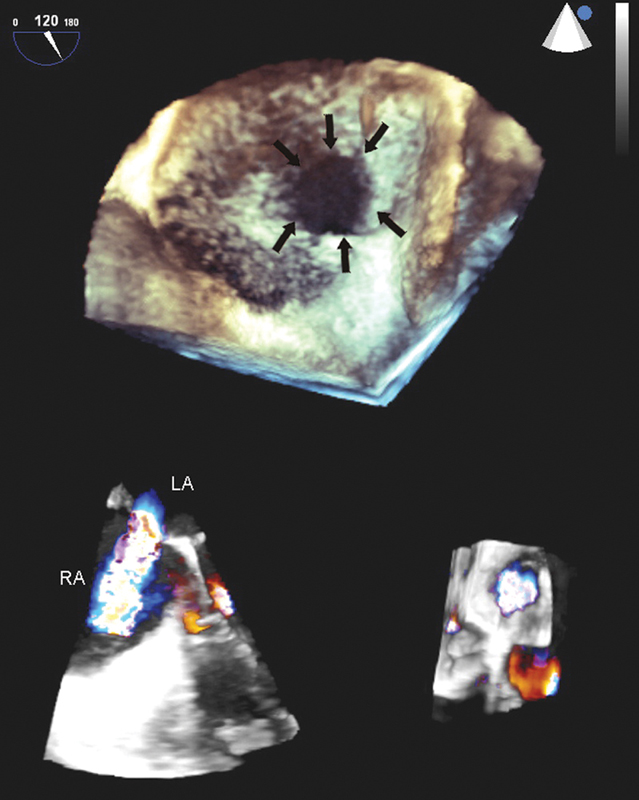

فحوصات تشخيصية لبعض امراض القلب والشرايين التاجية